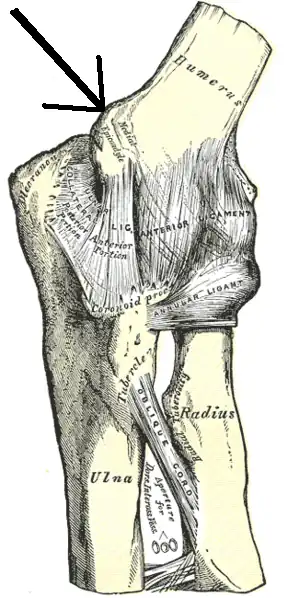

O epicôndilo medial do úmero é uma eminência localizada na extremidade distal do úmero, próximo à articulação desse osso com a ulna. É maior e mais proeminente do que o epicôndilo lateral. É onde se localiza o tendão comum que origina os músculos palmares antebraquiais superficiais, que são o pronador redondo, o flexor radial do carpo, o palmar longo, o flexor ulnar do carpo e o flexor superficial dos dedos. O epicôndilo ainda dá inserção ao ligamento colateral ulnar da articulação do cotovelo.[1]

No dorso do epicôndilo, existe um sulco por onde passa o nervo ulnar.[1]